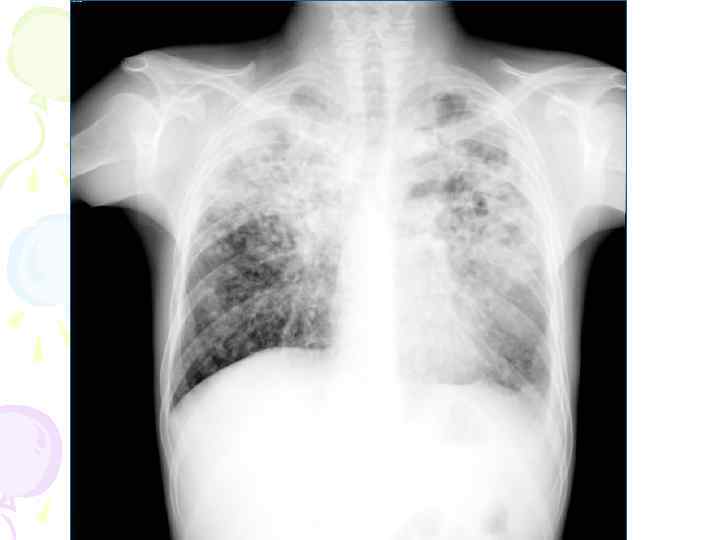

Рентгенологическая картина • множественные крупные / до 10 мм/ однотипные очаги преимущественно в верхних и средних отделах легких • Очаги округлой формы, малой и средней интенсивности, контуры нечеткие, часто расположены в виде цепочки вдоль продольных сосудов • Сливаясь, очаги образуют фокусы затемнения с участками просветления (распад) • При распаде в нескольких отдельных очагах формируются кольцевидные тени – штампованные каверны • При лимфогенной диссеминации очаговые тени с одной стороны, в средних и нижних отделах на фоне лимфангита, в корне кальцинаты